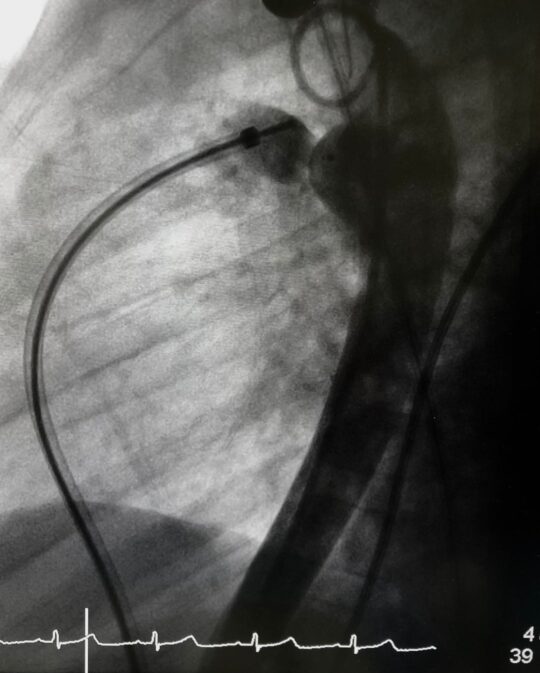

Device closure of PDA All About Heart And Blood Vessels

From johnsonfrancis.org

Device closure of PDA All About Heart And Blood Vessels Can Pda Close On Its Own A small patent ductus arteriosus may close on its own as your child grows. A pda that causes symptoms will need to be treated with medicine, cardiac. If doctors need to treat your baby's pda, they may: All babies have a pda in the womb. Babies and children with moderate and large sized. Larger pdas can cause extra blood to. Can Pda Close On Its Own.